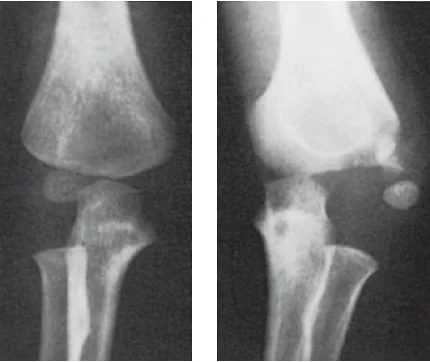

Stress Fractures

- Bone reacts to repeated loading, may become fatigued & a crack develops

- Fatigue fractures

- Abnormal stress or torque on a bone that has normal elastic resistance

- Examples:

- military recruits, athletes, ballet dancers

- Insufficiency fractures

- Normal muscular activity stresses a bone that is deficient in mineral or elastic resistance

Stress Fracture Details

- Usually Transvers

- 2nd metatarsal

- Tibia

- Fibula

- In osteopenia, osteomalacia

- Neck of femur

- Ribs

- Neck of humerus

- Scapula